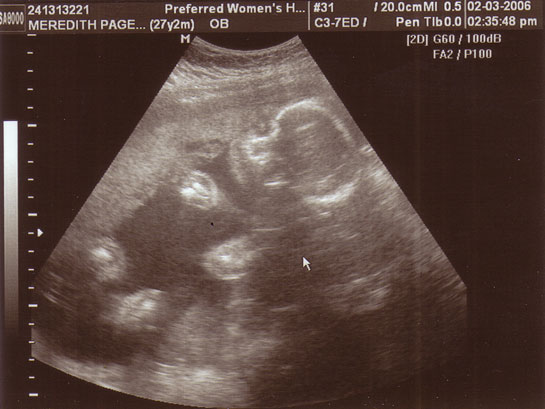

| 36 haftalık gebelik, bir hamilelik sürecinin önemli bir aşamasını temsil eder. Bu dönem, fetüsün gelişiminde kritik bir dönemdir ve anne adayının sağlığı bakımından da dikkate alınması gereken birçok faktör vardır. Bu makalede, 36 haftalık gebelik sürecinin özellikleri, anne adayı ve fetüs üzerindeki etkileri ile birlikte, bu dönemde dikkat edilmesi gereken konular ele alınacaktır. Fetüs Gelişimi 36 haftalık gebelikte fetüs, doğuma oldukça yakın bir dönemde bulunmaktadır. Bu aşamada fetüsün gelişimi ile ilgili bazı önemli noktalar şunlardır: